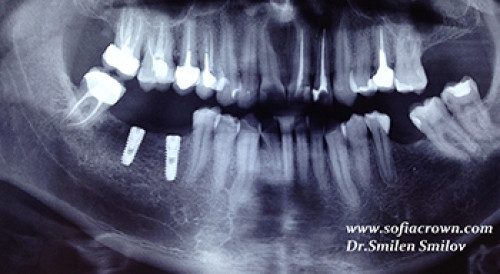

Поставени два зъбни импланта в областта на 46 и 47 в долна челюст.